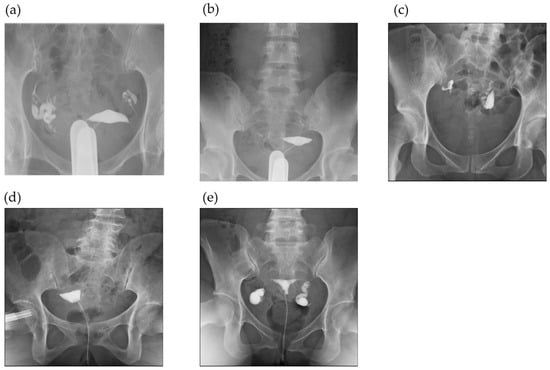

3.2. HSG Findings